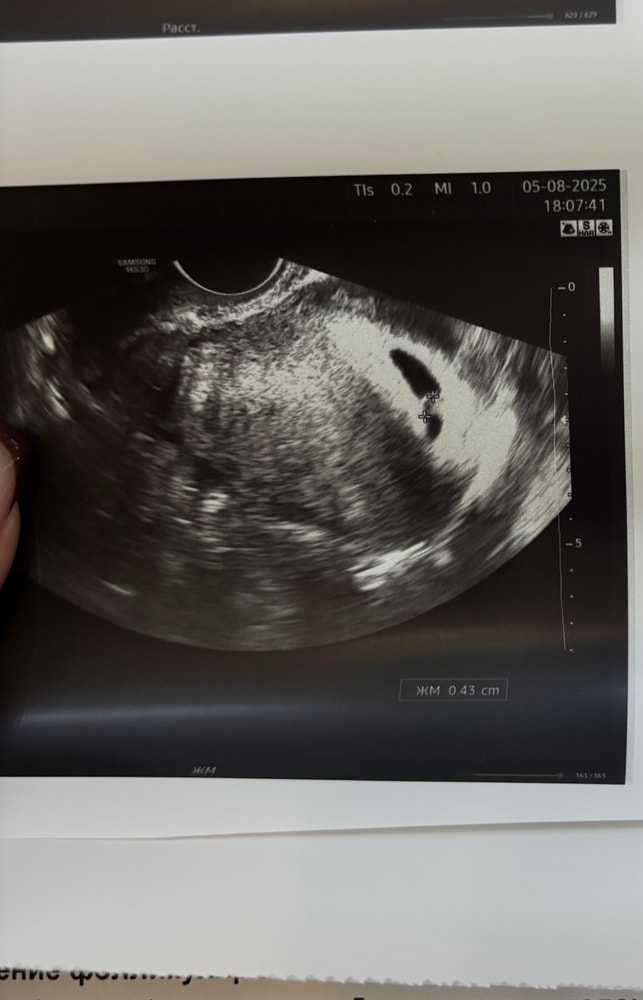

Девочки, кто сталкивался. Срок 6+2 по мес (по узи поставили 5н). Врач сказала тонус и угроза прерывания из-за тонуса и формы ПЯ. Сердцебиение есть, в целом периодически подтягивает живот, выделений нет. Чем у вас все закончилось?